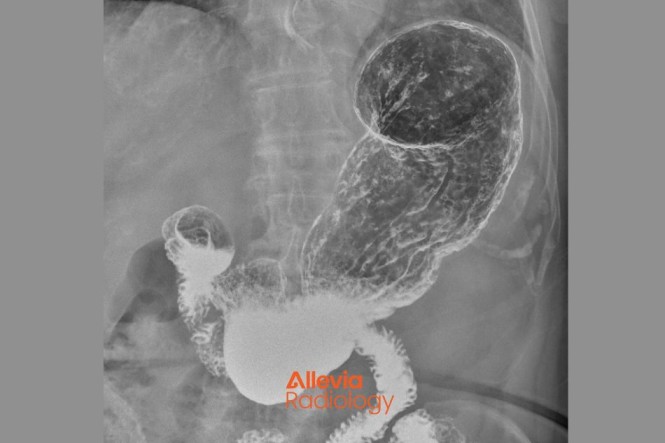

Healthify's radiology topics are brought to you in collaboration with Allevia Radiology (formerly Mercy Radiology).